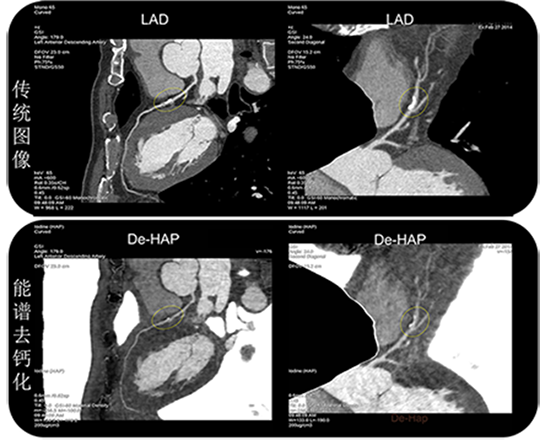

病例展示:曲面重建图像

传统图像显示: 左前降支(LAD)中段硬化斑块导致冠脉严重狭窄,约70%; 能谱去钙基图(De-HAP)清楚显示原狭窄段被严重夸大,实际仅为约15%的轻度狭窄 点评: 钙化(硬化斑块)是导致冠脉狭窄过度评估的重要原因。冠脉能谱去钙化是能谱技术在冠脉上的全新应用,可以有效预防冠脉狭窄的过度诊断,降低冠脉诊断的假阳性率,提高诊断的准确性

传统模式:左前降支(LAD)中段硬化斑块导致冠脉严重狭窄,约70% 能谱去钙化模式:轻度斑块狭窄,仅约15%